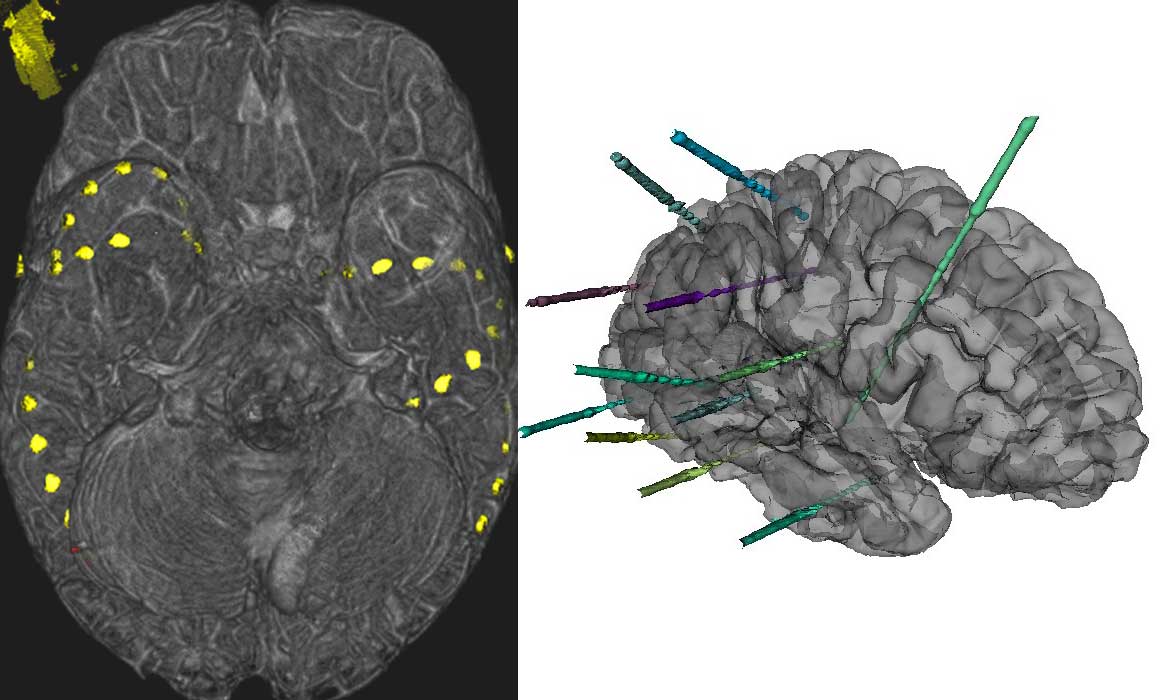

Senast Läkartidningen tog ett samlat grepp om epilepsi var 1997 i form av en serie. Mycket har hänt under de 20 år som förflutit. Nyligen presenterade International League Against Epilepsy en modifierad definition och klassifikation av epilepsi. Utveckling av dia­gnostiska metoder, bland annat förbättrad avbildningsteknik och genetiska test, har förfinat vår förståelse av orsaker till olika typer av epilepsi, men även påverkat rutiner för utredning av personer med misstänkt epilepsi. Ett stort antal nya antiepileptika har introducerats, vilket har förbättrat möjligheten till en individualiserad behandling. Detta har dock inte nämnvärt påverkat andelen patienter som blivit anfallsfria av läkemedelsbehandling, och därmed inte heller behovet av andra behandlingsformer som epilepsikirurgi, neurostimulering och kostbehandling. Under de år som gått sedan Läkartidningens serie publicerades har dessa metoder förfinats, och det vetenskapliga underlaget utvidgats. Status epilepticus måste kunna handläggas på varje akutmottagning. Även här har en ny klassifikation introducerats för att underlätta livsviktiga behandlingsbeslut.